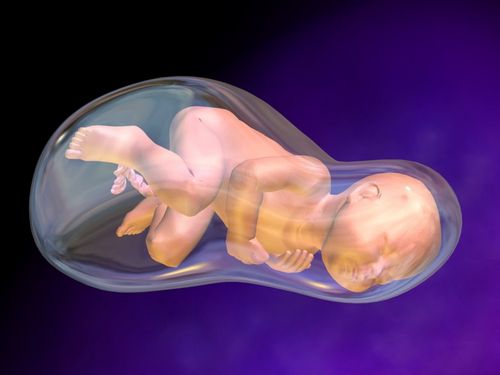

Навколоплідні води протягом всієї вагітності оберігають і створюють середовище для розвитку плода. До кінця вагітності цілісність плодового міхура порушується, і відбувається вилив вод.

Навколоплідні води необхідні малюкові. Значення їх неоціненне.

- Захищають від травм. Протягом всього періоду виношування малюка трапляються різні ситуації, однією з яких може стати пошкодження або удар в область живота. Наявність навколоплідної рідини убезпечить в критичний момент дитини і збереже вагітність.

- Сприяють активній фізичній діяльності малюка в утробі. Навички руху дуже важливі навіть для ще знаходиться всередині мами плода, адже від цього залежить розвиток плода. Вільні рухи стають можливі тільки при наявності нормального кількості рідини всередині плодового міхура. Захищають плаценту від травм при рухової активності дитини, а маму - від хворобливих ударів зсередини.

- Допомагають дитині зайняти правильне для пологів положення - головка в цьому випадку спрямована в бік родових шляхів.

При нормальній кількості вод дитина всередині матері відчуває себе комфортно і спокійно. Їх оновлення відбувається кожні три дні. Пошкодження цілісності плодового міхура завжди свідчить про закінчення виношування дитини. Щоб визначити початок пологів, важливо знати, як відбувається сам процес виходу рідини.